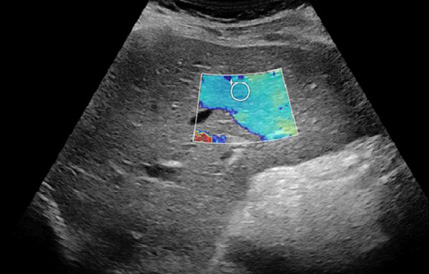

Представляем ряд клинических примеров, демонстрирующих определение степени фиброза печени с помощью SWE у беременных с HBV- и HCV-инфекциями (рис. 1–5).

Рис. 4. Беременная Б.Р., G3P2A0, позитивна по вирусу гепатита В, результат сдвигововолновой эластографии печени: METAVIRSTAGE — F3

Обследование проводили в положении пациентки на спине с уклоном влево. Датчик располагали в восьмом-девятом межрёберном промежутке по правой передней и задней подмышечной линии. Плотность ткани определяли в правой доле на бессосудистом участке на глубине 2 см от капсулы, результаты выражали в килопаскалях. Полученные показатели плотности тканей оценивали по шкале METAVIR: <7,1 кПa — F0–F1; 7,1–7,9 кПa — F2; 8,0–10,4 кПa — F3; >10,4 кПa — F4), где F0 — отсутствие фиброза; F1 — расширение портального тракта без септ; F2 — портальный фиброз с небольшим количеством сформированных септ; F3 — портальный фиброз с формированием множественных септ; F4 — цирроз печени.